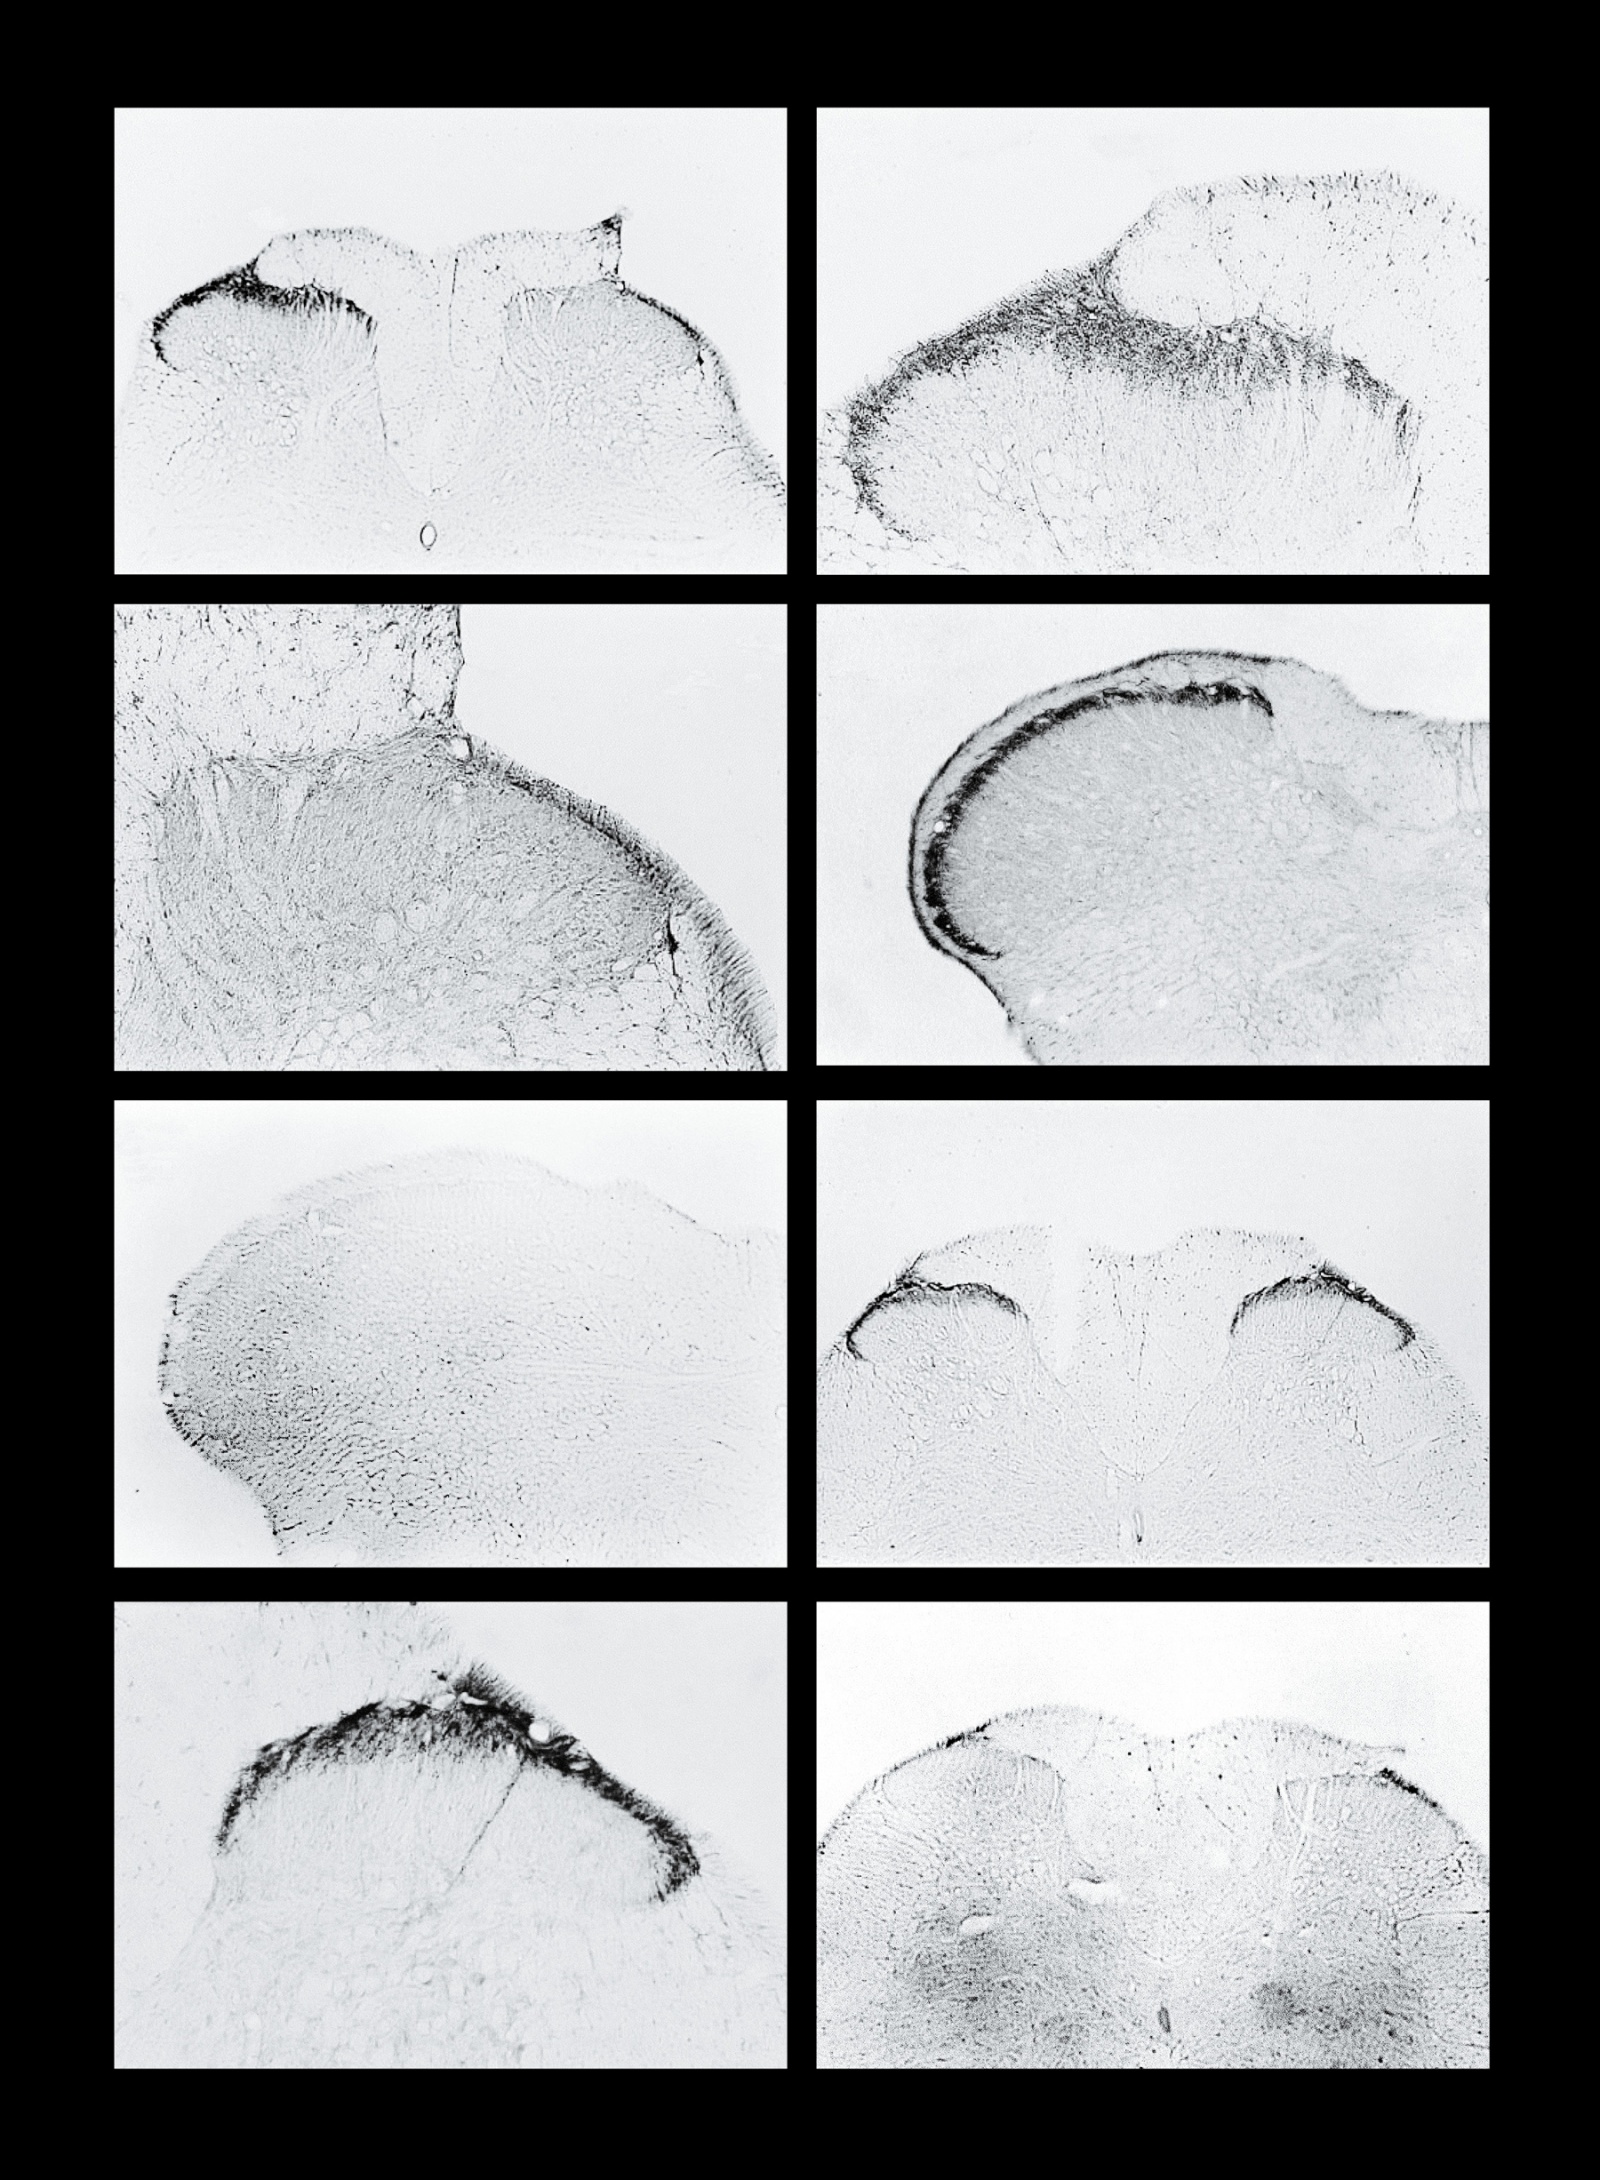

Болеутоляющая субстанция, эндоморфин, реагирует с клетками спинного крыс

Изображение из работы 1998 года, доказывающее присутствие эндоморфина в путях, по которым боль передаётся в